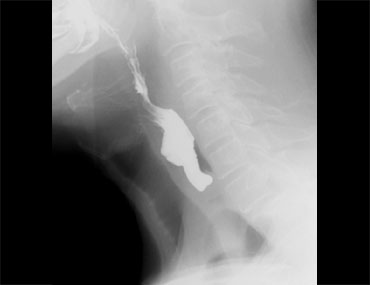

Các hình ảnh là của một bệnh nhân có cảm giác vướng họng (globus sensation).

Nguyên nhân là do trào ngược nặng và tình trạng tăng trương lực cơ nhẫn hầu thứ phát.

Thoát vị cạnh thực quản lớn kèm trào ngược là nguyên nhân gây ra các triệu chứng.